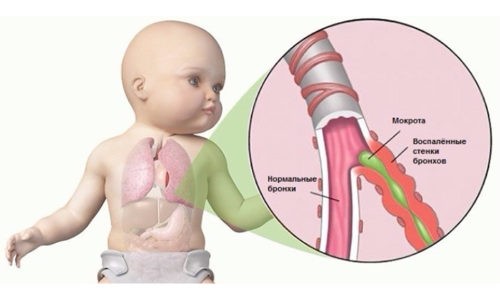

Бронхит у детей – это заболевание дыхательной системы, при котором воспалительный процесс поражает слизистую оболочку бронхов. Возникает при переходе болезни из острой формы в хроническую. Происходит это из-за отсутствия реакции родителей на симптомы, неправильно составленного лечения или осложнения после ОРВИ. Лечение хронического бронхита у детей проводится в домашних условиях, но имеет комплексный подход.